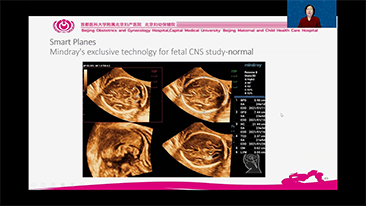

Geli?mi? ZST+ platformu ile desteklenen Nuewa'n?n tam kapsaml? ak?ll? ??zĂŒmleri, ?zellikle gebelik ?ncesi, gebelik ve do?um sonras? iyile?me sĂŒre?lerinde kad?n sa?l???n? iyile?tirmek, seviyeleri giderek daha da artan klinik zorluklar?n ĂŒstesinden gelmek i?in kapsaml? ve verimli tan?lar sunmak ĂŒzere tasarlanm??t?r.